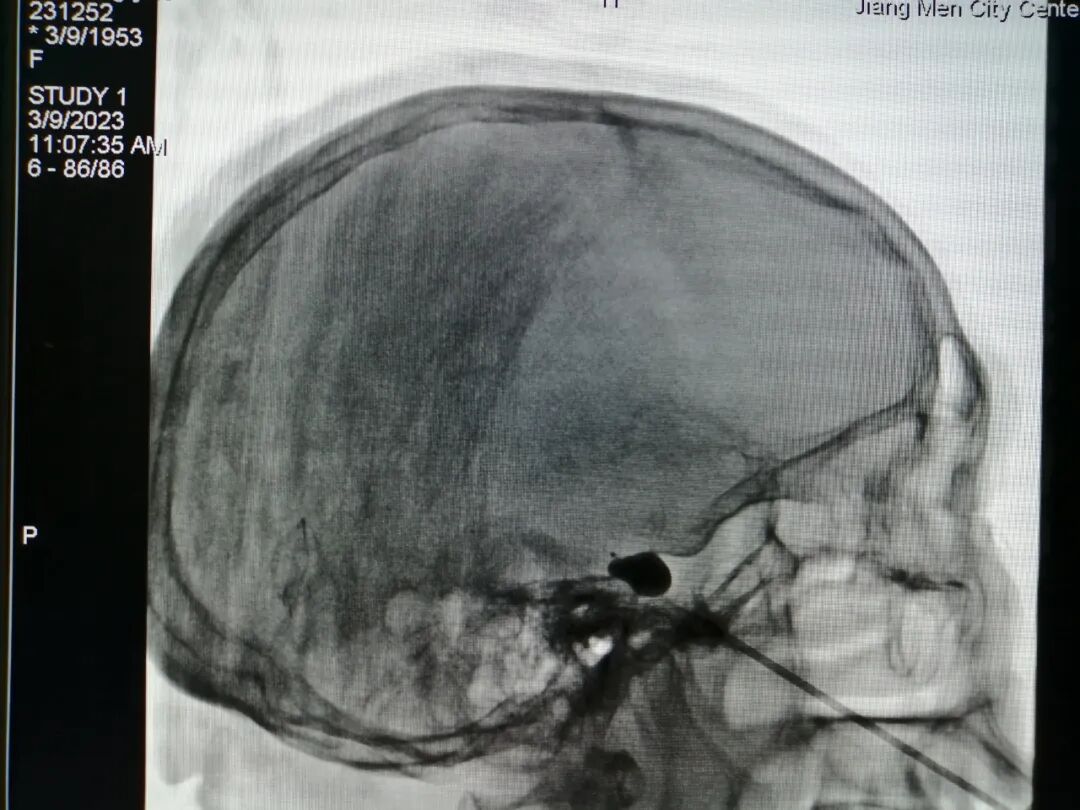

3.脊髓电刺激植入术

脊髓电刺激是一种先进的神经调控技术,通过将电极微创植入脊髓背侧,释放微弱电流干扰疼痛信号向大脑的传导,从而有效缓解顽固性神经病理性疼痛,尤其适用于复杂神经损伤痛。该技术具有可逆、可调、个体化等优势:患者可通过体外遥控器根据自身疼痛变化灵活调节刺激参数,实现个体化、动态的镇痛管理。

我院疼痛科于2022年1月成功实施江门地区首例脊髓电刺激植入术,为一位60岁饱受30余年神经痛及幻肢痛困扰的患者带来显著缓解;2024年8月,又率先完成五邑地区首例三叉神经半月节电刺激系统植入术,进一步拓展了神经调控技术在头面部顽固性疼痛中的应用,标志着我院在慢性疼痛微创与神经调控治疗领域持续走在区域前列。

△疼痛科为一名81岁左上肢急性带状疱疹神经痛患者行颈段脊髓电刺激术。

三叉神经半月节电刺激植入术